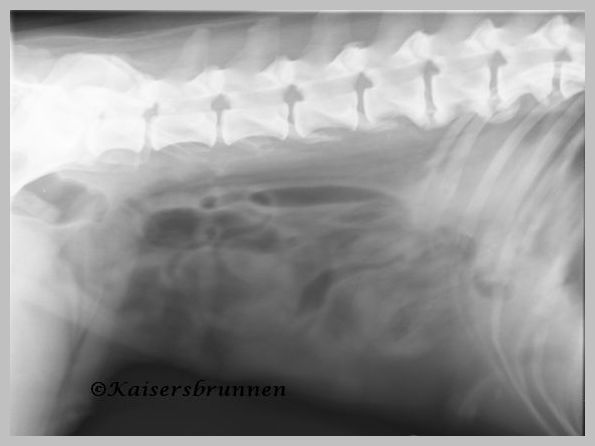

Unten aufgeführten Röntgenbilder sind von meiner Weißen

Schäferhunde Dame Delena,

sie wies auch im hohen Alter von 11 Jahren keinerlei Verkalkungen

oder Veränderungen in der Wirbelsäule sowie im

Hüftbereich auf.